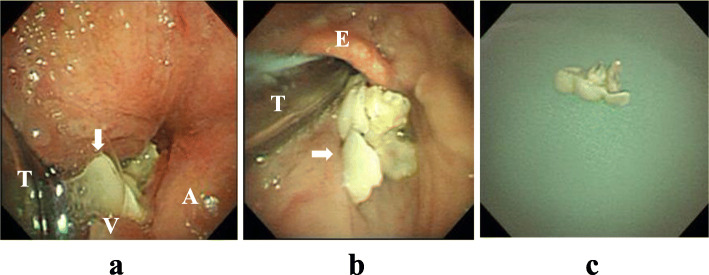

The patient entered the operating room while maintaining spontaneous breathing. After administration of atropine 0.5 mg, continuous administration of dexmedetomidine 0.22–0.89 μg/kg/h was started under standard monitoring as well as neuromuscular monitoring. In addition, ketamine 10 mg was administered seven times in total while observing the capnogram and the patient’s condition. Then, his respiratory rate became 12 breath/min, and he was sedated (Richmond Agitation-Sedation Scale score of − 2 to − 3). A total of 5 mL of 4% lidocaine was sprayed into the pharynx and larynx for local anesthesia via a Jackson’s spray. With the trachea intubated, the larynx was visualized using a blade size 4 of McGRATHTMMAC, and a bronchial fiber (OLYMPUS BF TYPE 1T260, tip outer diameter 5.9 mm, Olympus Corporation, Tokyo, Japan) was inserted into the oral cavity to observe the larynx. No foreign body was confirmed in the pharynx and larynx; however, when the bronchial fiber was inserted into the glottis from the gap between the glottis and the cuff of the tracheal tube, a part of the foreign body appeared and disappeared between the arytenoid cartilage and the vocal cord according to the patient’s breathing (Fig. 3a). Although we could not confirm the whole image of the foreign body, we were able to confirm that it was mobile. At this point, hiccups, cough, and/or gag reflex occurred and it became difficult to secure a field of view with the fiber. We judged that the foreign body could be removed via an oral approach using the bronchial fiber while maintaining intubation. Thus, rocuronium was administered to eliminate spontaneous breathing and body movement, and mechanical ventilation was started. After that, grasping forceps were inserted via the bronchial fiber, and the foreign body was pulled up to the pharynx. Then, it was removed using Magill forceps (Fig. 3b, c). Following the administration of sugammadex 200 mg, the patient’s respiratory condition returned to the preoperative level, and he was returned to the ICU. The surgery time was 35 min, the anesthesia time was 51 min, the lowest percutaneous oxygen saturation during the procedure was 93%, and there was no bleeding associated with the removal procedure.

Fig. 3.

Photographs taken with a bronchial fiber. a A foreign body (arrow) was located between the vocal cord (V) and the arytenoid cartilage (A) outside of the tracheal tube (T). b The foreign body during the removal procedure. The foreign body (arrow) was pulled up between the tracheal tube (T) and epiglottis (E). c A removed crown bridge, whose backing metal was covered with resin. It consisted of three connected teeth with a pointed edge